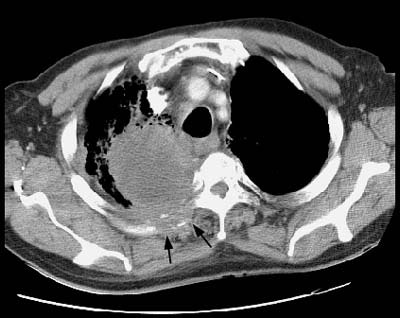

Example 2: This patient with a squamous cell superior sulcus tumor demonstrates obvious rib destruction and mass invading the chest wall (black arrows). There is loss of the tissue plane between the mass and the mediastinum and along the anterior aspect of the vertebral body which suggests mediastinal invasion as well (T4 lesion).